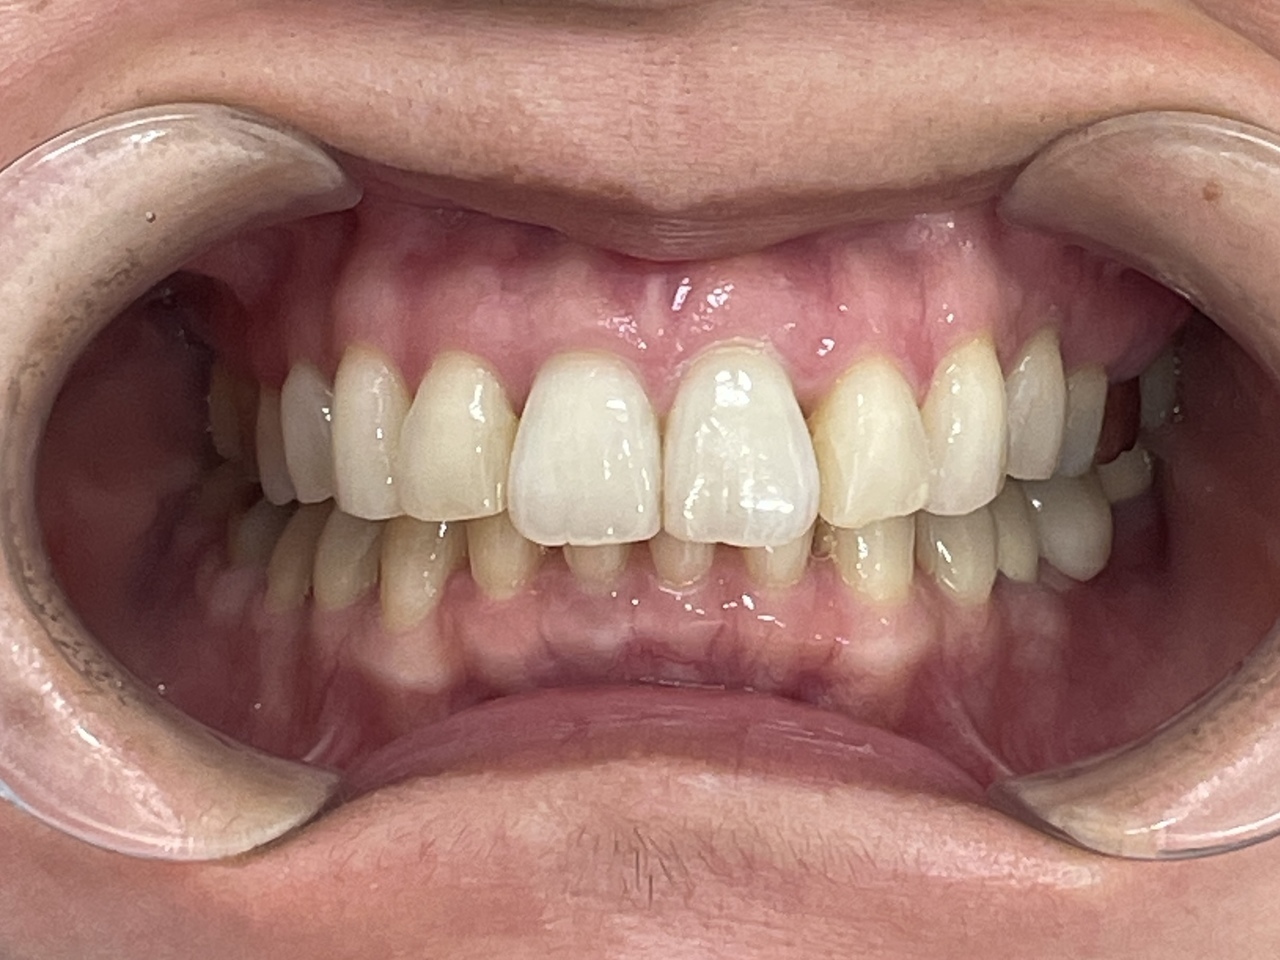

Before

After

矯正の種類 / invisalign GO

年齢・性別 / 30代男性

主訴  /  上下顎前歯の叢生

治療期間 / 16ヶ月

費用 / 簡易検査 5,000円(税別) 精密検査 30,000円(税別)

両顎マウスピース 450,000円(税別) 両顎リテイナー料 40,000円(税別)

※マウスピース交換時別途調節料5,000円(税別)

副作用 / 口内炎・歯の移動に伴う痛み・知覚過敏 ※数日で収まる場合が多いです

リスク / 後戻り防止の為、夜のみマウスピースで保定を指示